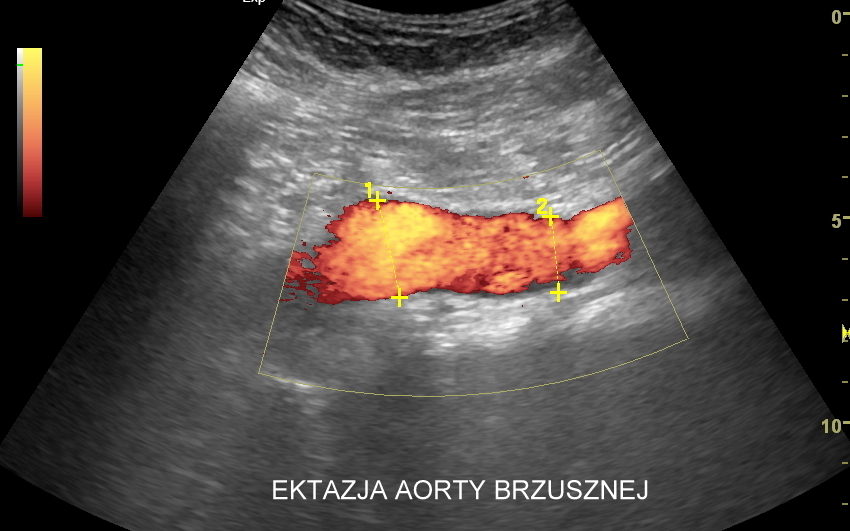

USG aorty i tętnic biodrowych

Badanie USG Doppler aorty brzusznej i tętnic biodrowych jest częścią standardowego USG jamy brzusznej. Nierzadko wykonywane jest jednakże jako badanie celowane w przypadku oceny tętniaków aorty brzusznej i tętniaków tętnic biodrowych, rozwarstwień aorty, zwężeń miażdżycowych występujących na podziale aorty lub w obrębie właściwych tętnic biodrowych. Funkcjonalne badanie aorty i tętnic biodrowych przeprowadza się także w ramach diagnostyki zaburzeń wzwodu i bólów zlokalizowanych w pośladkach. W pracowni dr Szczepańskiego zbadać można również w USG aortę piersiową w zakresie aorty wstępującej, łuku aorty i aorty zstępującej. Otóż należy mieć na uwadze, iż w obrębie aorty piersiowej lokalizować mogą się takie schorzenia jak tętniaki, rozwarstwienia, koarktacja aorty, czy choroby zapalne.